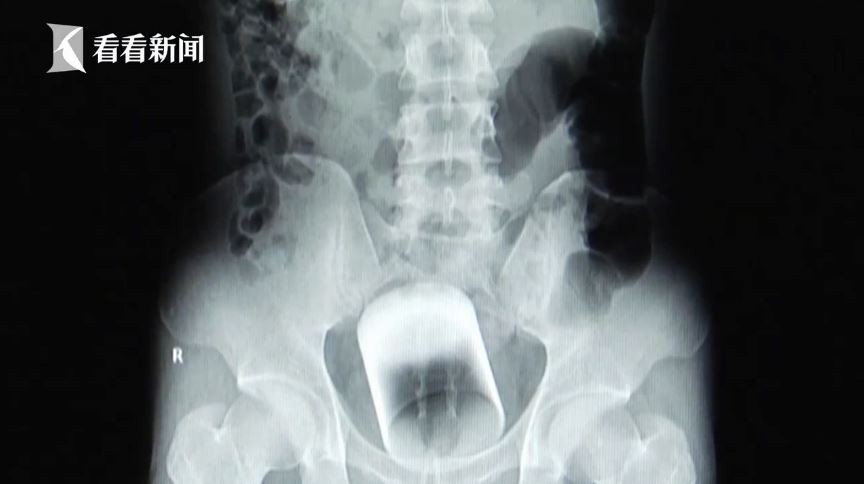

在中國廣州有一名31歲的已婚男子,他有天跑去醫院求助,表示自己的肛門感到非常腫脹,醫生照了X光後才發現,在男子的體內有著一個不明的圓柱體,直徑約7公分左右,一問之下才知道該物品是個「玻璃杯」!

在該名男子的骨盆腔內、直腸中段,有著一個倒放的廣口玻璃杯,離肛門有一小段距離,幸運的是直腸看起來沒有出血等嚴重問題。醫生原本打算直接從肛門取出該玻璃杯,但是這只能用手去拿取,而無法用圓鉗,一方面擔心會不小心傷到彎曲的直腸,或是不小心造成玻璃杯碎裂。